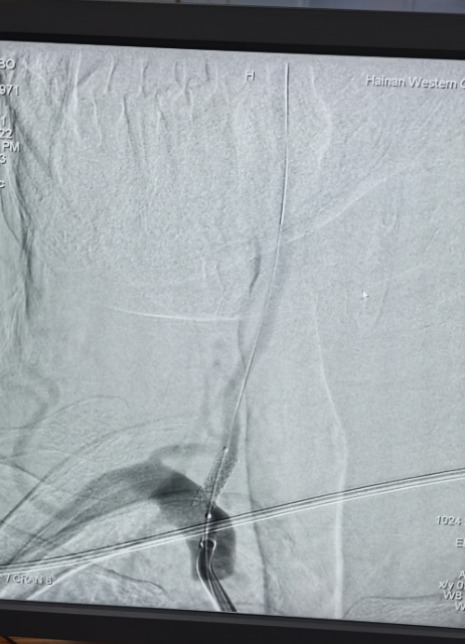

男性,76岁。因长期头晕、头昏,来到海南西部中心医院就诊。查超声提示双侧颈动脉重度狭窄,脑血管造影提示左侧颈内动脉百分之九十以上狭窄,右侧颈动脉百分之七十五以上狭窄。据悉,这种患者年脑梗发生率百分之二十以上,急需进行介入手术治疗。

术前DSA

神经内科介入团队在术前根据患者实际情况,制订了周密的术前预案,并与患者家属充分沟通,在得到家属支持并同意手术后,为患者实施了左侧颈动脉球囊扩张支架植入术。不到一个小时的时间,手术顺利完成,精确地将支架置于患者左侧颈动脉狭窄处,使其恢复正常血运,成功转危为安。